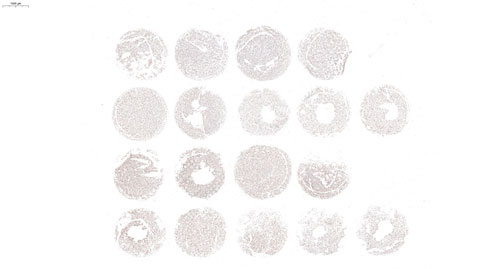

H腫瘤細胞芯片-PCNA

H腫瘤細胞-PCNA染色